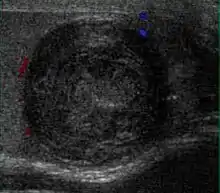

Sonography of a normal testis. The normal testis presents as a structure having homogeneous, medium level, granular echotexture. The mediastinum testis appears as the hyperechoic region located at the periphery of the testis as seen in this figure.

The normal adult testis is an ovoid structure measuring 3 cm in anterior-posterior dimension, 2–4 cm in width, and 3–5 cm in length. The weight of each testis normally ranges from 12.5 to 19 g. Both the sizes and weights of the testes normally decrease with age. At ultrasound, the normal testis has a homogeneous, medium-level, granular echotexture. The testicle is surrounded by a dense white fibrous capsule, the tunica albuginea, which is often not visualized in the absence of intrascrotal fluid. However, the tunica is often seen as an echogenic structure where it invaginates into the testis to form the mediastinum testis. In the testis, the seminiferous tubules converge to form the rete testes, which is located in the mediastinum testis. The rete testis connects to the epididymal head via the efferent ductules. The epididymis is located posterolateral to the testis and measures 6–7 cm in length. At sonography, the epididymis is normally iso- or slightly hyperechoic to the normal testis and its echo texture may be coarser. The head is the largest and most easily identified portion of the epididymis. It is located superior-lateral to the upper pole of the testicle and is often seen on paramedian views of the testis. The normal epididymal body and tail are smaller and more variable in position.